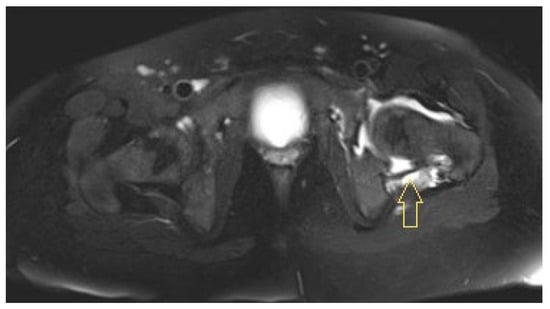

3.1.1. Patient 1

3.1.2. Patient 2

3.1.3. Patient 3

4.3. Diagnostic Imaging